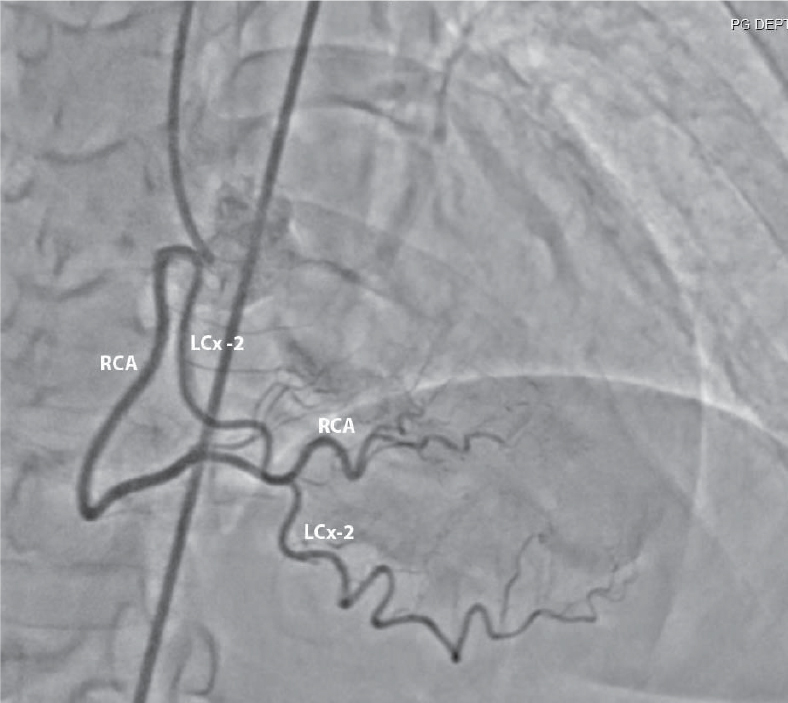

Figure 2. Right coronary angiogram showing second left circumflex artery (LCx-2) arising from right coronary artery (RCA).

Echocardiography revealed hypokinetic inferolateral wall. Elective coronary angiography was then planned, which showed twin LCx arteries: one originating from LMCA and the other from the proximal RCA (Figs. 1 and 2). Patient was discharged on optimal medical therapy and he remained asymptomatic in follow-up period.